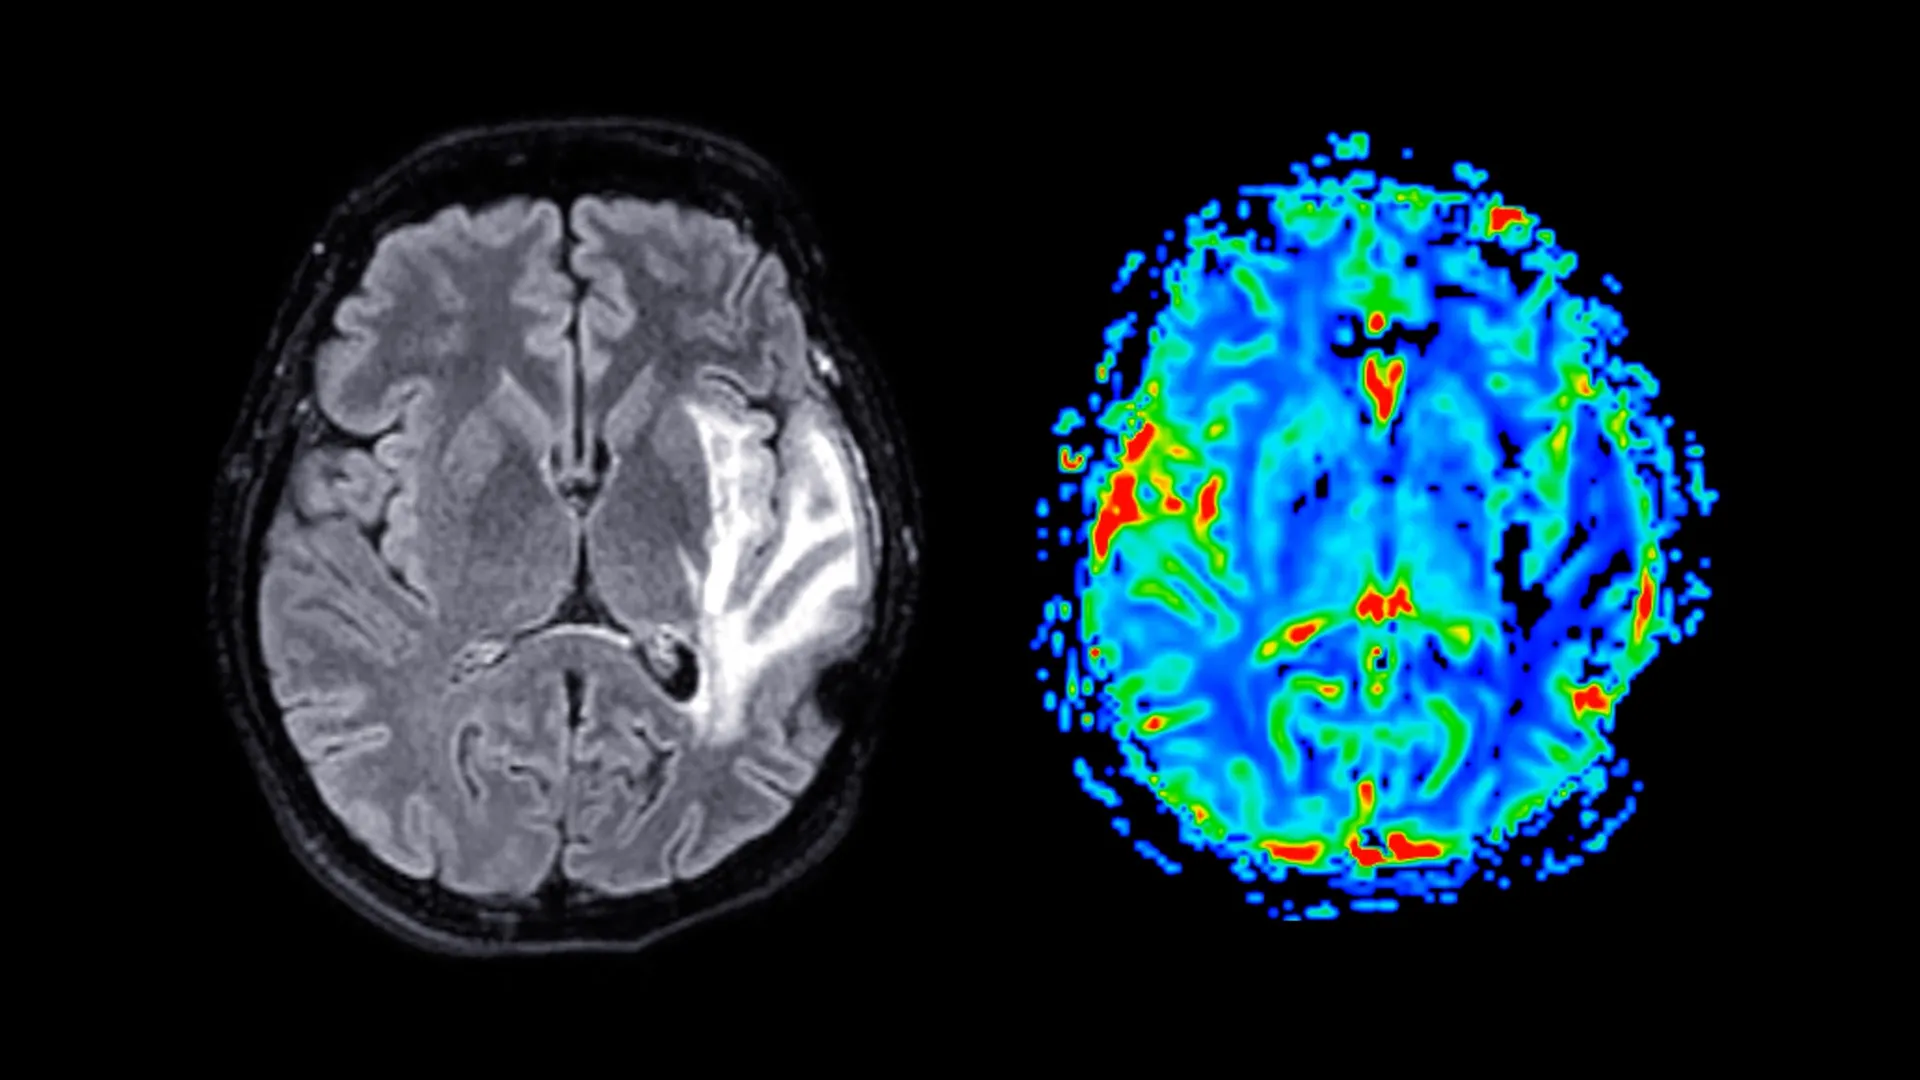

يعد الخرف مصدر قلق عالمي متزايد للصحة العامة، ولا يوجد علاج له حاليًا. يعاني الأشخاص المصابون بهذه الحالة من انخفاض خطير في القدرات العقلية، بما في ذلك الذاكرة والتفكير، والتي يمكن أن تتداخل بشكل كبير مع الحياة اليومية.

ويشير الخرف إلى مجموعة من اضطرابات الدماغ وليس إلى مرض واحد. الأشكال الأكثر شيوعًا هي مرض الزهايمر والخرف الوعائي والخرف المختلط. تؤدي هذه الحالات إلى تلف الخلايا العصبية في الدماغ تدريجيًا، وتتفاقم الأعراض بمرور الوقت. ومع تقدم المرض، قد يواجه الأشخاص صعوبة في الذاكرة واللغة وحل المشكلات والتغيرات في السلوك.